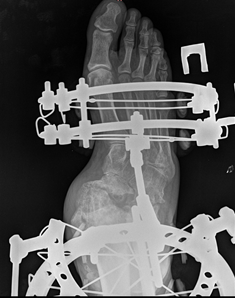

39-летний зауралец поступил в НМИЦ ТО имени академика Г.А. Илизарова Минздрава РФ с приобретенной плосковальгусной деформацией обеих стоп на фоне псориаза. Пациент с 2017 года состоит на учете у ревматолога с диагнозом – псориатический артрит, это системное заболевание, которое сочетает воспаление суставов с кожными проявлениями, такими как псориаз. Прогрессирующая патология вызвала сложную деформацию стоп и боли в голеностопном суставе, из-за которых мужчина не мог самостоятельно передвигаться и утратил опорную функцию ног. Консервативное лечение по месту жительства не дало положительных результатов. Встать на ноги помогли врачи Клиники нейроортопедии и системных заболеваний Центра Илизарова.

«Терапия пациента включала два последовательных этапа. Первым шагом стало наложение аппарата Илизарова на правую голень и стопу, это позволило постепенно скорректировать деформацию, – отметил лечащий врач, к.м.н. Андрей Неретин, – затем была проведена стабилизирующая операция (панартродез) на стопе. В данный момент пациент находится на этапе фиксации и выписан домой, демонтаж аппарата ожидается примерно через 2,5 месяца».

Со слов лечащего врача, основное заболевание внесло свои корректировки в ход лечения. Наличие очагов псориаза на нижних конечностях существенно осложняло ведение пациента. Поскольку риск инфицирования после операции был повышен, первоочередной задачей стало купирование острой фазы псориаза и снижение воспаления мягких тканей, только после этого стало возможным проведение хирургического вмешательства.

Несмотря на тяжелую металлическую конструкцию на стопе, пациент из Курганской области свободно передвигается. Это дает хорошие перспективы для дальнейшего лечения, в планах – операция на левой ноге, которая также деформировалась вследствие псориатического артрита.